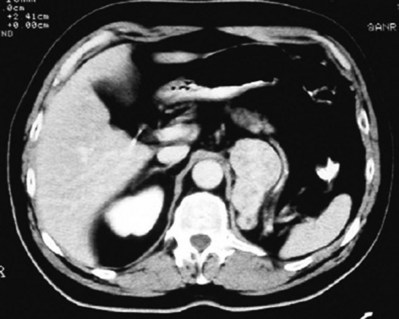

In addition to causing pain, cysts may compress the renal parenchyma or other adjacent organs, cause ureteral obstruction and obstructive uropathy, spontaneously bleed, cause hypertension, or become infected. Laparoscopic decortication or unroofing may be used to treat these cysts, which are typically simple in character (Fig. 55–22). Cysts with complex appearance, such as thickened septa, calcification, or enhancement (Bosniak class III-IV), may be explored and sampled laparoscopically to rule out renal cell carcinoma due to their increased risk of harboring malignancy (Cloix et al, 1996; Santiago et al, 1998). Options include cryoablation, enucleation, partial nephrectomy, or radical nephrectomy. If there is any question of cyst proximity to the collecting system, cystoscopy and placement of an open-ended ureteral catheter may be performed to ensure the integrity of the collecting system after cyst excision.

Figure 55–22 Axial CT scan in delayed phase after IV contrast administration, demonstrating peripelvic cysts in a patient who presented with left flank pain.